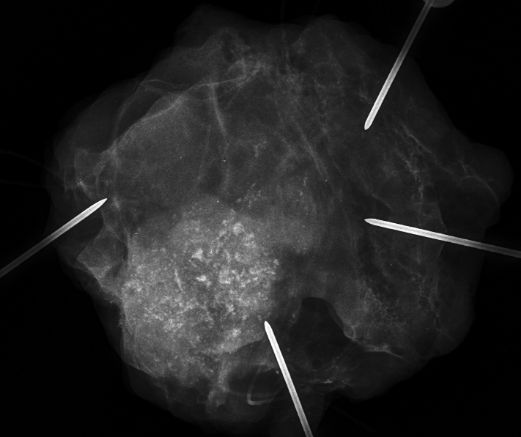

| DCIS | 80-jähriger Mann mit einem Knoten rechts retromamillär. Mammographie: Dichter Knoten mit multiplen Mikroverkalkungen unmittelbar periareolär. Histologie: papilläres DCIS, G2, 19 mm, ER: 12/12, PR: 6/12, Ki-67: 20%. Th.: Exzision, Radiatio der Mamma, TAM über 5 Jahre | ||||

Präparat![]() | |||||